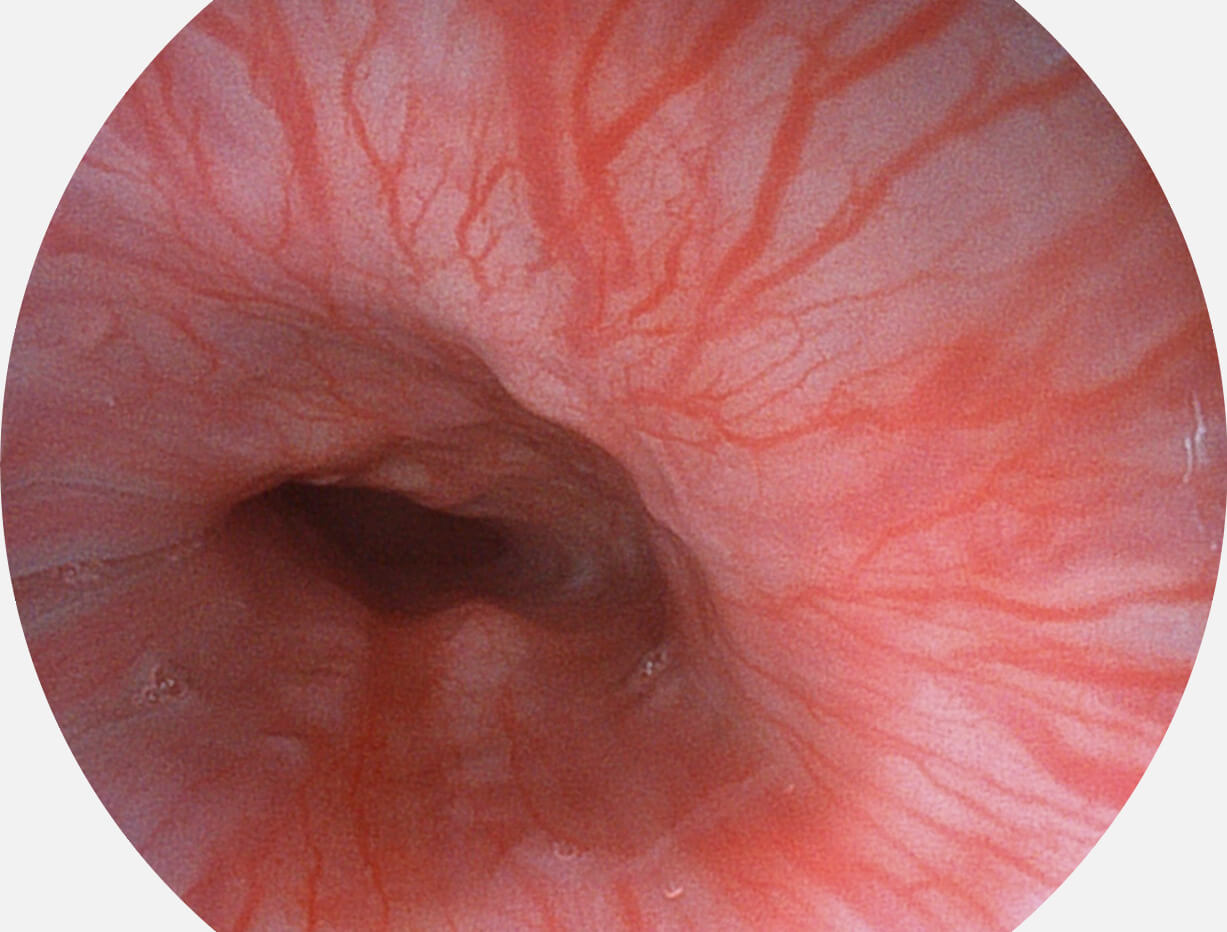

Versatile Intelligent Staining Technology, VIST

强调浅层黏膜结构的同时,保证照明亮度和提升浅层微血管与中层血管颜色对比度,病变边界更清晰。

VIST图像